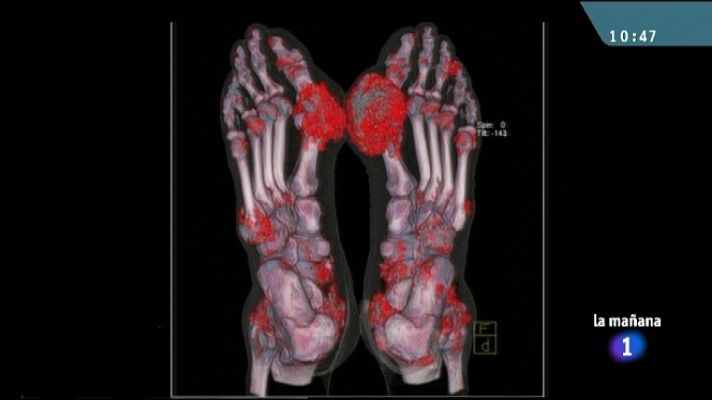

Ácido úrico al final del año

Ácido úrico al final del año